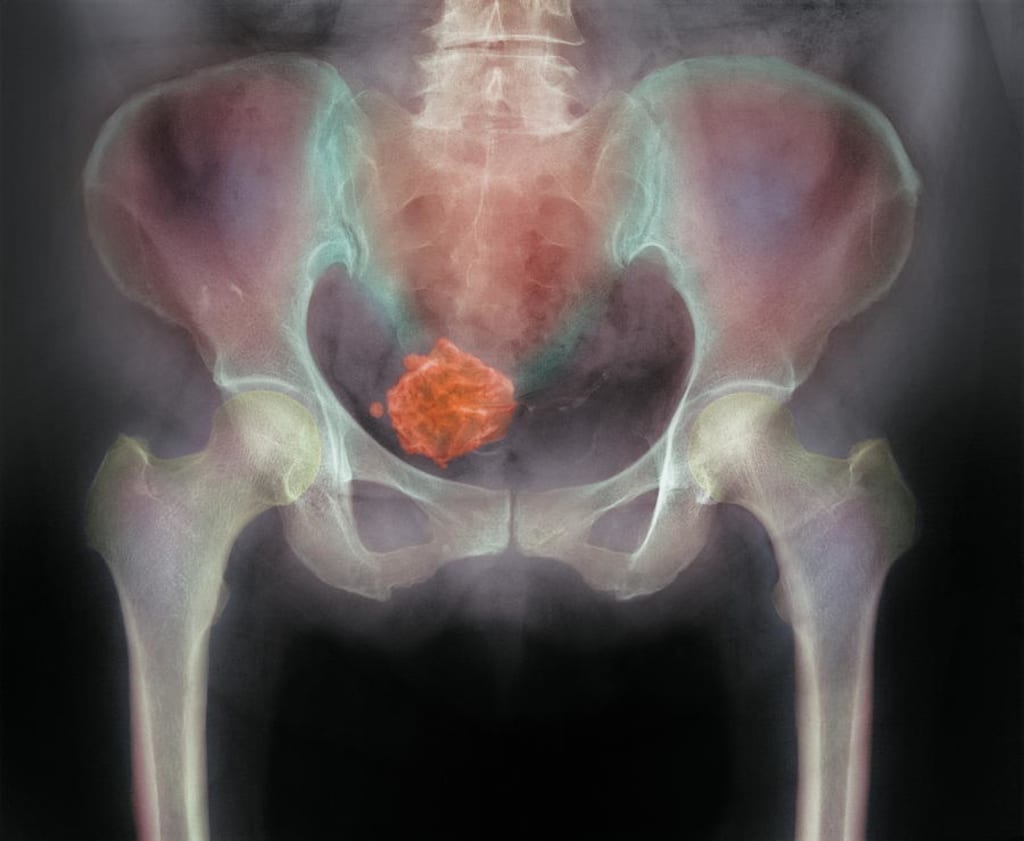

At a younger age I learned that I had fibroid's when I first learned I thought that my womanhood was over but with a lot of prayer and a lot of research I learned that a woman could live with them all her life and that they had to be managed with not only diet but healthy choices. I have stuck to a plant base diet. I had done the research again. I even bought a book called Healing Fibroid's A doctors Guide to a Natural cure, Book's picture as seen above.